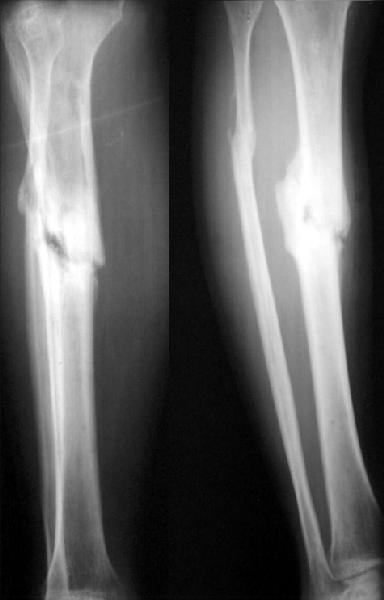

No hollow reamers and nails are still availble yet, so UTN 10 mm was used. After perQ osteotomy of the fibula i tried to open the canal, and the awl was passed to the distal fragment only after closed mobilization of the site to make some antecurvation. It resulted with some anterior translation of the distal fragment :( After impaction the nail was locked dynamically. Images attached. Comments/critics are

welcome.

get_image.jpg

16KB (17241 bytes)

I agree. The non-union looks like a 'stiff hypertrophix non-union'. So, leave the nail in-situ. Remove the distal inter-locking screws. Apply an Ilizarov frame and initially distract and later compress. Luckily, the fibula has not united.

I believe this nailed nonunion of the tibia shaft will likely go on to uneventful healing. Good job.

I'm not clear if you opened the fracture site and used an awl or if you used an awl through the nail entry site. The latter is preferred although often difficult and sometimes impossible.

Today the case was criticized at the week clinical report for the antecurvation deformity... Unhappily our vice-director tries to prove that such a malalignment is of great clinical importance.

I would expect the deformity of the case of nailed tibia shaft nonunion (slight apex posterior and slight posterior translation) to be of no definite and small theoretical clinical importance.